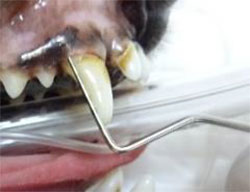

上左写真がスケーリングをした後の口腔鼻腔瘻管になっている部分です。歯と歯のすき間がかなり広がり、見た目にも大きな穴が空いているようにも見えます。実際にその部分の抜歯をしますと、上右写真のようにたくさんの膿が溜まっていて、それを全て掻き出している状態です。

上写真がスケーリングをした後の口腔鼻腔瘻管になっている部分です。歯と歯のすき間がかなり広がり、見た目にも大きな穴が空いているようにも見えます。実際にその部分の抜歯をしますと、下写真のようにたくさんの膿が溜まっていて、それを全て掻き出している状態です。